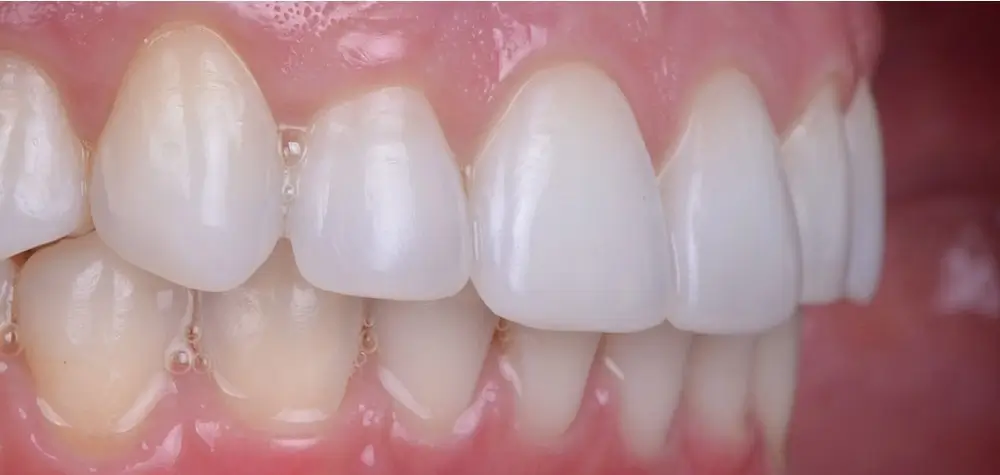

Дистальный прикус - Кейс 4

Эффективность устранения дефекта прикуса посредством элайнеров FlexiLigner.

Результаты лечения